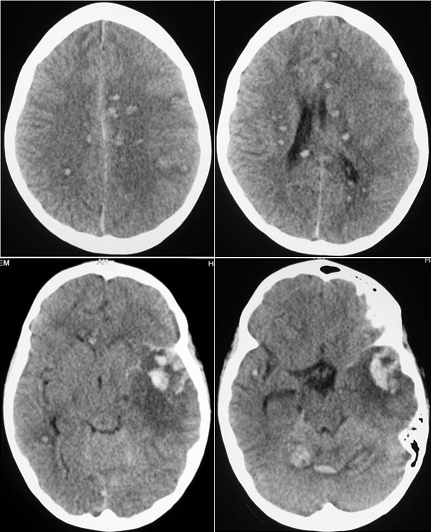

The 11-year old girl presented a diagnosis of viral hepatitis A confirmed by anti-HVA IgM. Eight 8 weeks after, she developed hemorrhagic syndrome coupled with fever associated and persistent jaundice. The blood count showed aregenerative pancytopenia secondary to aplastic anemia confirmed by bone marrow biopsy. During conditioning for allogenic bone marrow grafts, the patient developed generalized seizures revealing disseminated intracerebral hemorrhage (pictures). There was a favorable outcome after blood transfusions and resuscitation. Hematological complications in hepatitis A are rare. Although intracerebral hemorrhage resulting from Hep A has never been reported in the literature; its occurrence is directly correlated with the degree of thrombocytopenia due to aplastic anemia. The prevalence of aplastic anemia in viral hepatitis is estimated at 0.1%. This complication implies systematic hematological evaluation in cases of viral hepatitis A; especially in severe forms or those associated with involving cholestasis.